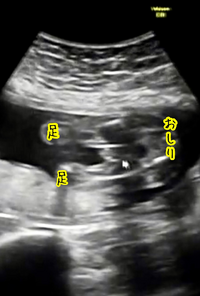

エコー写真 性別の見分け方 男の子女の子別エコー 妊娠週まとめてみました ママびよりウェブ